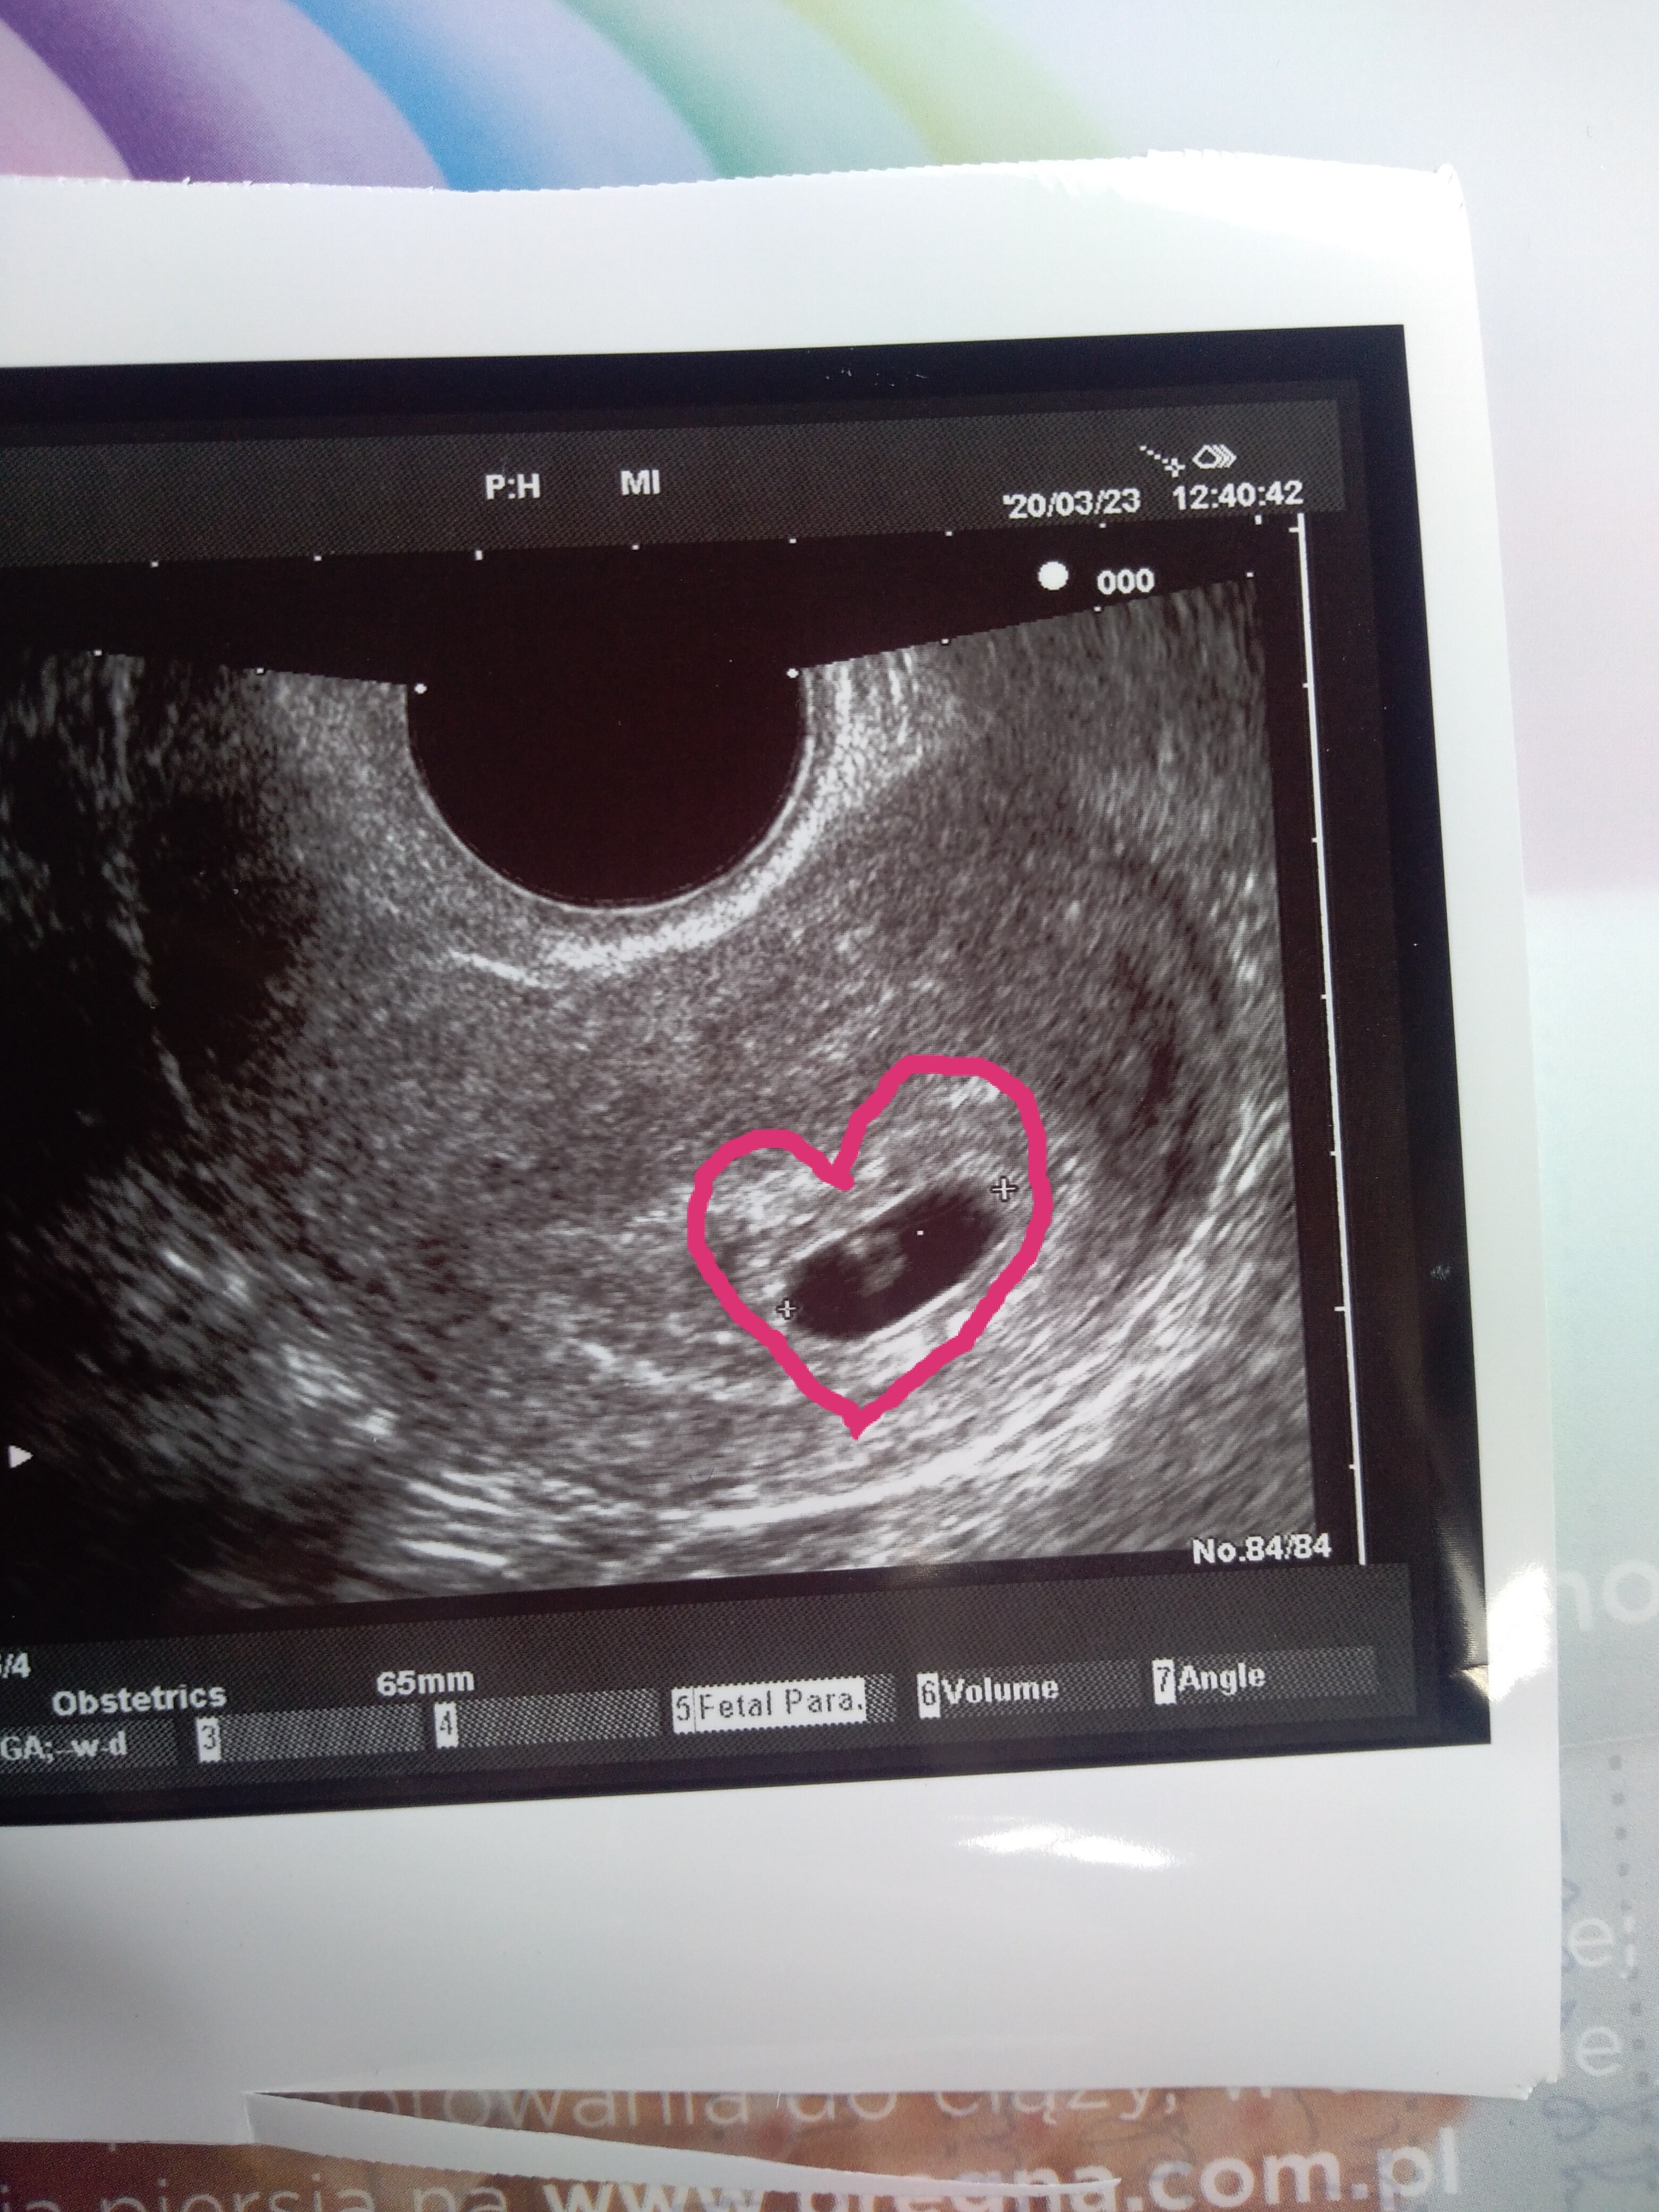

Gratulacje!Ja już po wizycie. Na szczęście tym razem póki co wszystko dobrze. Serduszko już biłowedług usg 6+5.